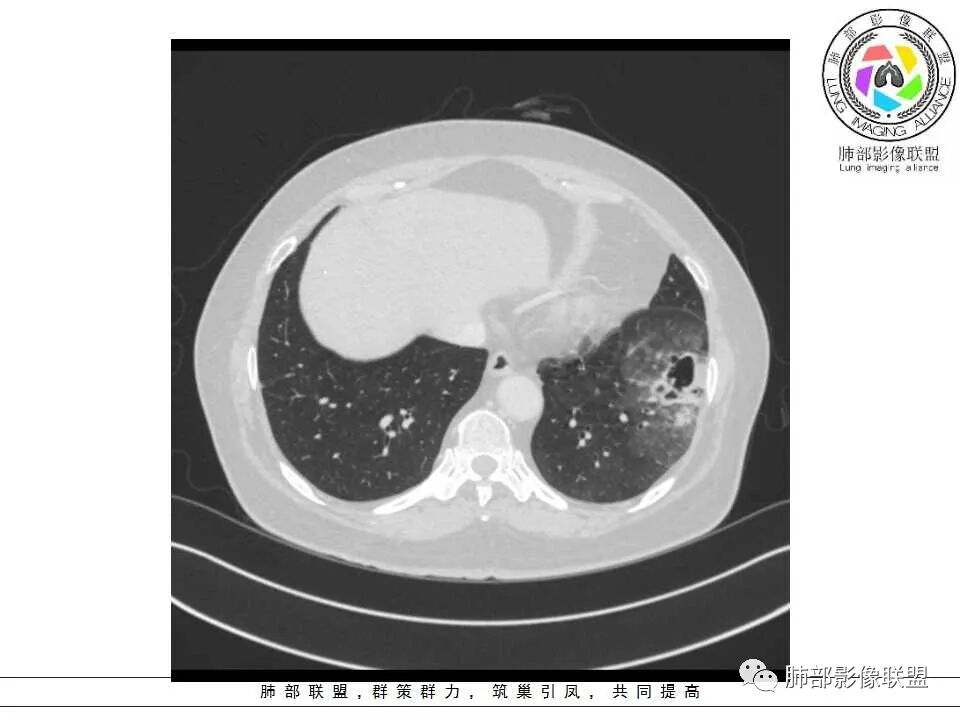

左肺下叶不规则空洞,周围边界清楚磨玻璃影,空洞内可见丝状物及壁结节,空洞壁薄,真菌感染和肿瘤难以分别,倾向感染

女性,65岁,左肺下叶空腔边缘见不规则结节,结节强化轻、不均匀,局部坏死边界较清楚,胸膜为糊墙为主,膈面胸膜判断不清楚似有结节;空腔内见分隔,或者数个融合,局部张力稍弱,边缘见支气管截断和血管集束;外周见大片磨玻璃影,部分边界模糊。结合病史炎症肯定有,但是囊腔结节这部分感觉恶性征象多过良性,考虑囊腔型腺癌可能性大,鉴别肺大疱感染

左肺下叶外侧基底段空洞,壁增厚,轻度强化,周围磨玻璃影,边界清晰,考虑囊腔型肺癌。

左肺下叶见薄壁囊腔影,周围呈磨玻璃样改变,囊腔形态欠规整,囊壁见小结节影,考虑感染性病变,除外囊腔型腺癌。

左肺下叶囊性空腔影,内分隔,壁不均匀,周围磨玻璃边界清楚,胸膜牵拉。倾向腺,鉴别真菌感染。

老年女性,咳嗽、咳痰2月余,CT提示:左肺下叶可见一不规则结节,周边可见磨玻璃密度,边界清,内可见囊腔样改变,内可见分割,内壁不规则,部分可见分叶,引流支气管狭窄,走形僵直,轻度强化,考虑囊腔型腺癌,鉴别曲霉、结核等

老年女性,受凉后咳嗽咳痰发热两天,近两天咳嗽加重。CT示左肺下叶不规则空洞伴局部洞壁结节,空洞内见分隔,似见扩张支气管相通。空洞周边伴大片磨玻璃影。结节与胸膜宽基底相连,轻度强化,考虑为囊腔型腺癌伴感染

左肺下叶空洞结节,薄壁,局部可见壁结节,支气管于边缘走形中断,周围磨玻璃影,边界不清。先考虑感染,鉴别囊腔腺癌。

老年女性,左下肺病灶,空洞,璧厚薄不均,内有壁结节,周围磨玻璃,边界清,符合假大空,考虑腺癌。

患者老年女性,受凉后咳嗽,咳痰,发热,左肺下叶不规则空洞结节,周围大片磨玻璃影,倾向恶性。

这个病例,老年女性,边缘磨玻璃,中间假大空,磨玻璃边界清楚,腺癌

假大空,壁结节,磨玻璃影=腺癌

右肺下叶假大空,内可见分隔,壁不规则,周围大片磨玻璃影,部分边缘模糊,胸膜受累增厚,肝脏多发囊肿,考虑囊腔型腺癌。

老年人,左肺下叶囊性病变+实性结节+磨玻璃影,尽管病灶相邻胸膜反应较广泛,但是上述影像表现及临床症状,首先考虑肺癌(腺癌),相邻胸膜反应广泛有可能为肺癌合并感染性病变所致。

女性,65岁,咳嗽、咳痰2月余,伴发热数日。

胸CT:左肺下叶囊腔,壁厚薄不均,可见壁结节,囊腔内可见断裂小梁,部分融合,周围边界较清楚GGO,胸膜牵拉,可见血管集束、支气管充气征,冠状位部分层面可见支气管在囊腔边缘截断。考虑:囊腔型腺Ca。鉴别:肺大疱感染,CPAM等。

1、左肺下叶外基底段不规则囊腔样病灶,囊腔内有条形影及血管穿行。

2、囊壁薄厚不均匀,稍显僵硬,有壁结节(对应边缘分叶等)、结节强化明显。

以上两条几乎将肺囊肿彻底排除在外,且高度怀疑新生物!

3、灶周环以大范围磨玻璃影,非常均匀,没有重力分布趋势,分叶状,边界隐约可变。

4、冠状位部分层面可见支气管在囊腔边缘截断。